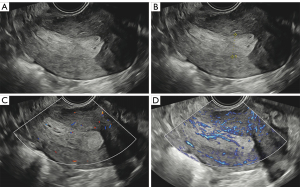

Figures 4,5 show the typical ultrasonic images of a nonmalignant endometrium. Figure 4 depicts the ultrasonic images of endometrial hyperplasia. The vascularity in the endometrium was scored higher on MVFI (score =2) than on CDI (score =1). Figure 5 provides ultrasonic images of endometrial polyps. The vascularity in MVFI was more abundant (score =4) than that in CDI (score =3).

Abundant vascularity was observed in endometrial malignancy, as depicted in Figures 6,7. Specifically, Figure 6 shows the high vascularity in focal atypical hyperplasia. The subjective score was higher for MVFI (score =4) than for CDI (score =2). A similar outcome can be observed in Figure 7, which shows endometrioid adenocarcinoma. CDI showed moderate vascularity (score =3), while MVFI showed abundant vascularity (score =4). MVFI exhibited more abundant vascularity in both nonmalignant and malignant endometria as compared with CDI.